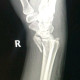

Alo dok, saya ada kenalan pasien yg kemarin mengalami KLL jatuh dari motor dengan lengan kanan menghantam aspal dan jatuh sekitar 3 meter dari motor. Sudah di rontgen IGD dan didapatkan Fraktur komplit comminuted radius distal dengan angulasi volar. Meskipun sudah diedukasi berulang kali, keluarga pasien bersikeras tidak mau dioperasi secepatnya.

Menurut dokter, bagaimana cara menjelaskan ke pasien ya dok, mereka ttp menginginkan di urut terlebih dahulu. Mohon sarannya dok, thanks